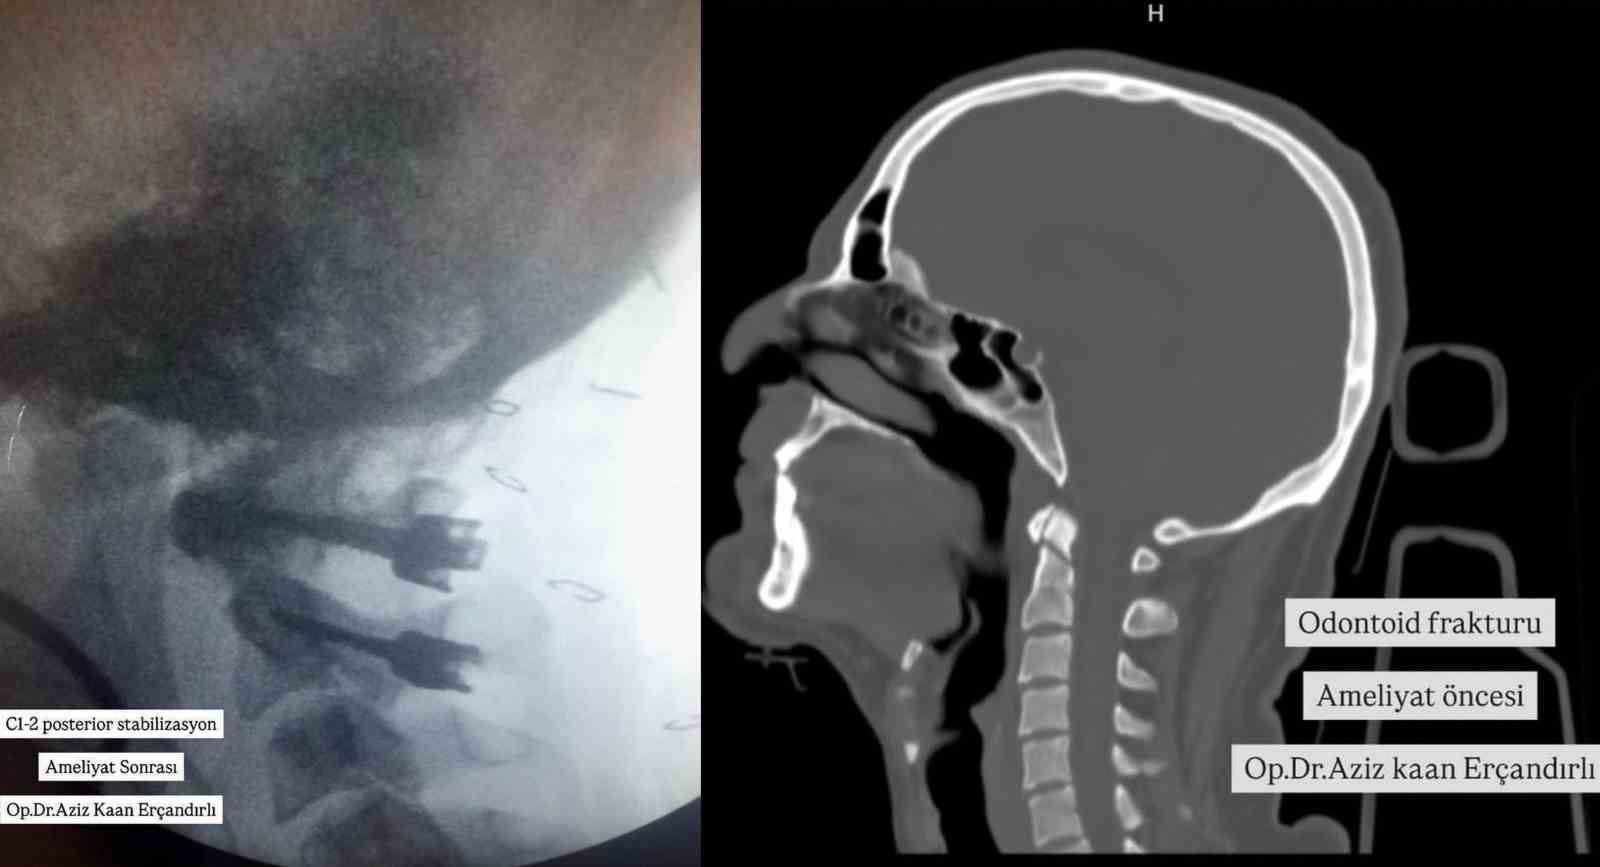

Bayburt Devlet Hastanesinde ilk kez C1-2 posterior stabilizasyon yapıldı

Yüksekten düşme sonrası vücudunda kırıklar oluşan bir hastaya Bayburt Devlet Hastanesinde ilk kez C1-2 posterior stabilizasyon başarıyla yapıldı.

Konuya ilişkin hastanenin sosyal medya hesabı üzerinden yapılan açıklamada, "Bu hastamızda yüksekten düşme sonrası odontoid tip 2 kırığı olması üzerine Bayburt’ta ilk defa C1-2 posterior stabilizasyon yapıldı. Odontoid çıkıntı, kafatabanı ve boyun bileşkesi geniş hareket becerisi açısından önemli bir parçasıdır. Böylesi geniş hareket aralığı ile birlikte stabilitenin idamesi de ayrı bir özellik taşımaktadır. Bu yüzden odontoid kırıkları servikal kırıklar içinde önemli bir yere sahiptir. Çoğunluğu yüksek enerjili travmalarla oluşur ve sıklıkla zorlayıcı fleksiyon ve/veya ekstansiyon hareketleri sonucu oluşmaktadır. Boyun Kırığı Ameliyatı Beyin ve Sinir Cerrahisi Uzmanımız Aziz Kaan Erçandırlı tarafından başarılı bir şekilde gerçekleştirilmiştir." ifadelerine yer verildi.